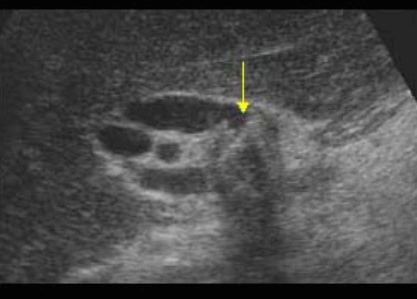

US finding

- 담낭관 또는 담낭 경부에 결석이 확인된다.

- 총간관(CHD) 또는 담낭관(cystic duct)의 확장소견이 보인다.

- 간내외 담관의 확장이 관찰된다.